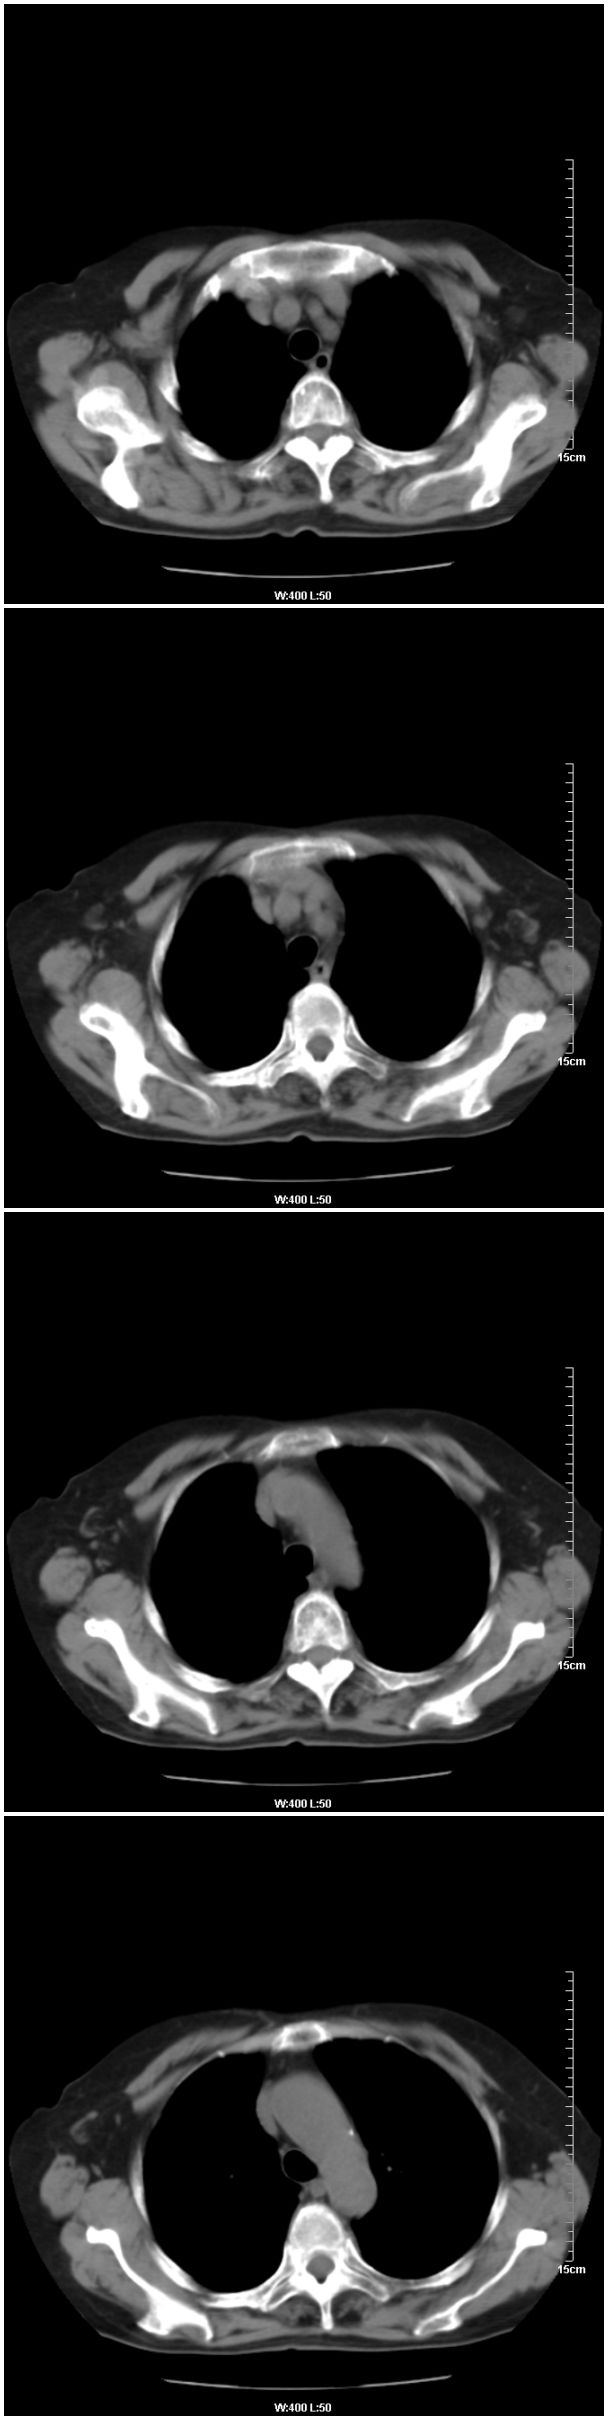

女性,78岁。术前体检发现肺部病变,看看还有什么问题?肺病变是什么性质?

在右侧,支持!右肺中心型肺癌! 右乳腺肿物。

支持!右肺中叶中心型肺癌!右侧乳腺内上象限结节,建议薄扫

乳腺病变在右侧,右肺门区新生物伴右中叶阻塞性肺炎、部分部张

右肺中叶不规则肿块,管腔阻塞,心包内少量积液,支持右肺中心型肺癌。

应该是右肺中心型肺癌,乳腺的肿物应该在右侧,看见右侧有结节,并乳头凹陷

右肺中央型肺癌伴中叶肺不张。